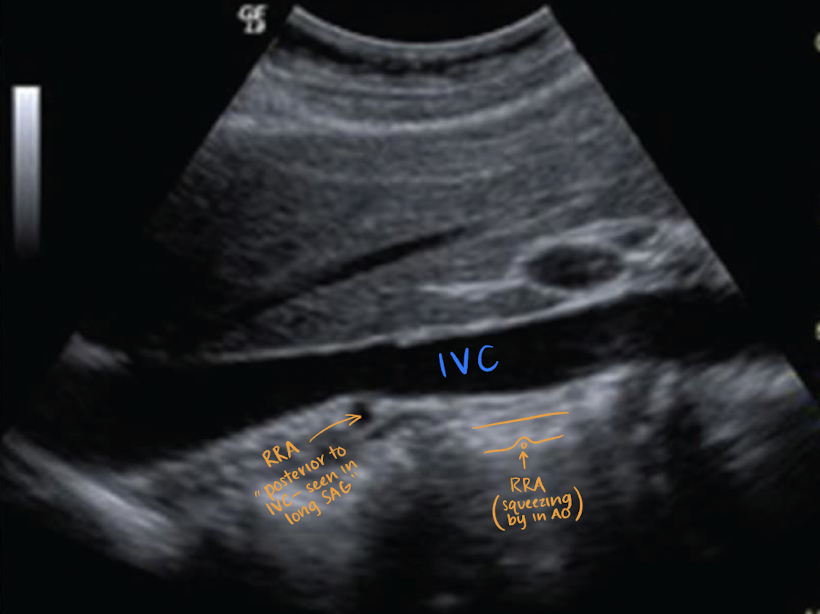

renal arteries (RRA and LRA)

inferior to SMA

courses horizontally to supply the kidneys

RRA

RRA is longer than LRA and courses posterior to IVC (goes excuse me under the IVC)

??